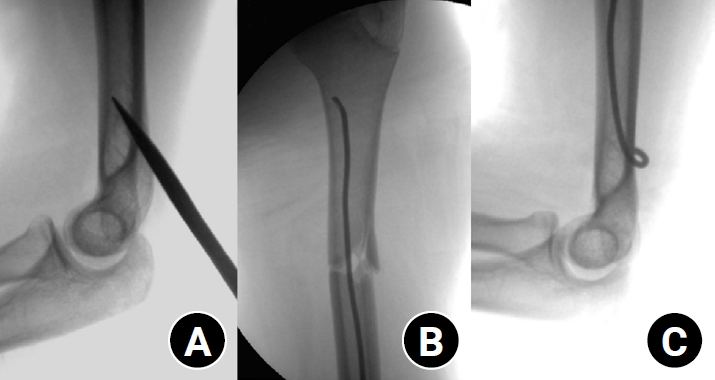

A posterior entry technique through the distal humeral cortex was used in all cases. A small longitudinal incision was made over the posterior aspect of the distal humerus just proximal to the olecranon fossa. The triceps muscle was bluntly split to expose the posterior cortex, and an awl was used under fluoroscopic guidance to create the entry portal into the medullary canal (Fig. 1).

Fig. 1.

Intraoperative fluoroscopic images demonstrating the surgical technique of elastic stable intramedullary nailing for a pediatric humeral shaft fracture. (A) The entry point was created at the posterior cortex of the distal humerus using an awl under fluoroscopic guidance. (B) The prebent elastic nail was advanced across the fracture site under continuous fluoroscopic visualization. (C) The distal ends of the nails were contoured and buried subcutaneously to minimize soft-tissue irritation.

Fig. 1. Intraoperative fluoroscopic images demonstrating the surgical technique of elastic stable intramedullary nailing for a pediatric humeral shaft fracture. (A) The entry point was created at the posterior cortex of the distal humerus using an awl under fluoroscopic guidance. (B) The prebent elastic nail was advanced across the fracture site under continuous fluoroscopic visualization. (C) The distal ends of the nails were contoured and buried subcutaneously to minimize soft-tissue irritation.